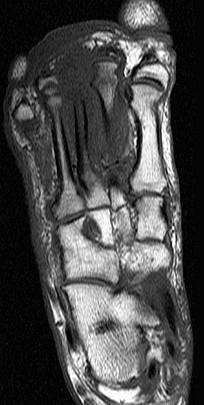

女,55岁,第3趾肿胀,结合图像,最可能的诊断是 ( )A、结核B、化脓毒性关节炎并骨髓炎C、未见异常D、骨髓炎E、化脓性关节炎

问题 女,55岁,第3趾肿胀,结合图像,最可能的诊断是 ( )

选项 A、结核 B、化脓毒性关节炎并骨髓炎 C、未见异常 D、骨髓炎 E、化脓性关节炎

答案 B